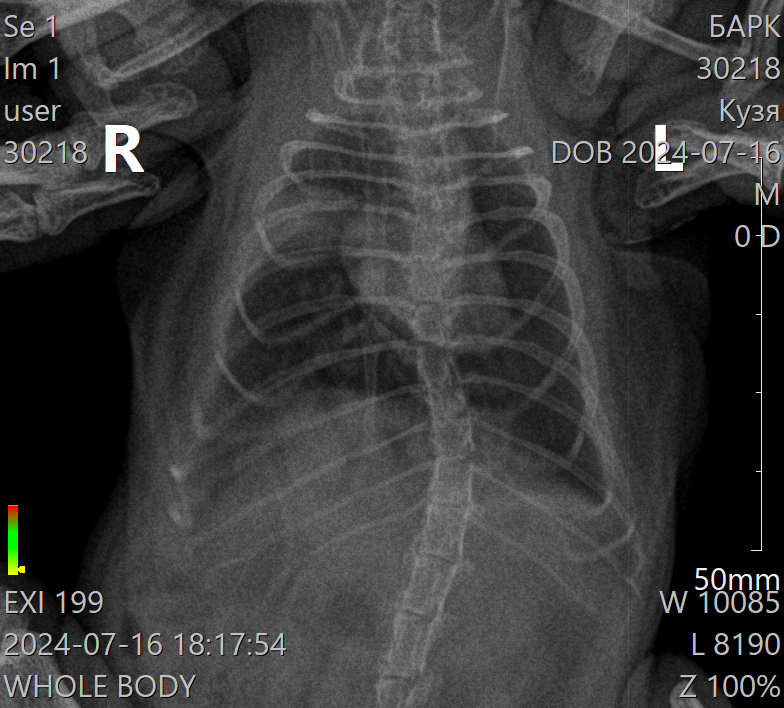

Ездили к ветиринару, сделали рентген. По снимку врач сказала что есть поражение и оно уже хроничесское. Вылечить уже не получиться. Прописала имуномодулятор Трекрезан 200мг 1/40 2 раза в день.